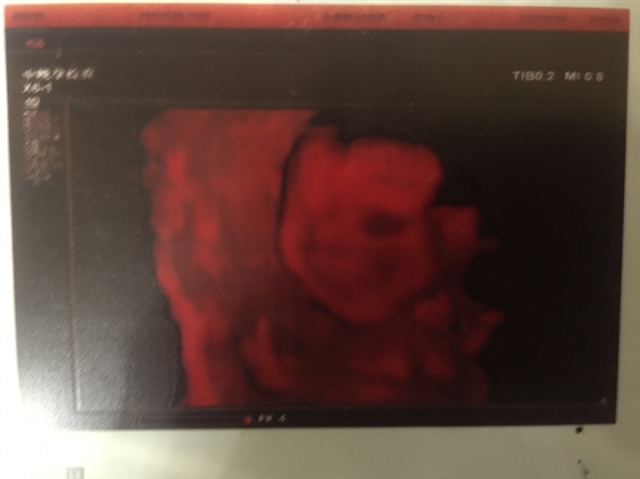

宝宝4个月2天

孕13周+2天

男孩